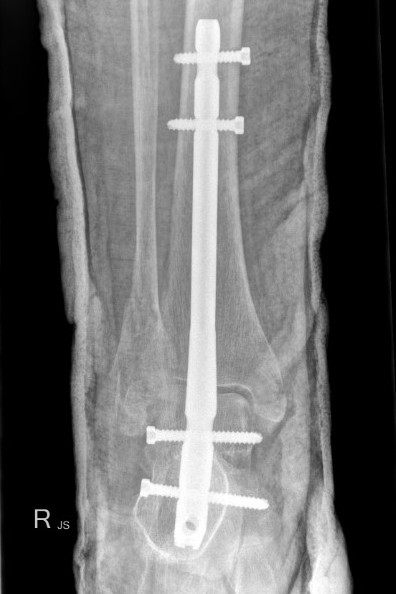

Hindfoot nail

Indications

Fragility fracture / osteoporosis

Compound wound

Poor skin

Co-morbidities - diabetes, smoking

Technique

Insertion point

- in line with 2nd metatarsal / center of heel pad

- junction of posterior 2/3 and anterior 1/3 heel

- should pass through anterior aspect posterior subtalar joint

- posterior to lateral plantar artery and nerve

Screw fixation

- distal screw fixation in calcaneum +/- talus with jig

- compression

- proximal screws medial to lateral